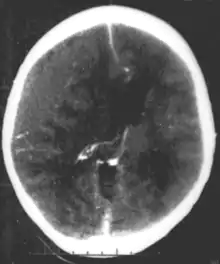

Brain trauma in the developing human is a common cause (over 400,000 injuries per year in the US alone, without clear information as to how many produce developmental sequellae)[41] of neurodevelopmental syndromes. It may be subdivided into two major categories, congenital injury (including injury resulting from otherwise uncomplicated premature birth)[6] and injury occurring in infancy or childhood. Common causes of congenital injury are asphyxia (obstruction of the trachea), hypoxia (lack of oxygen to the brain), and the mechanical trauma of the birth process itself.[42]